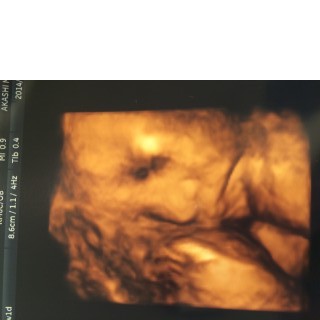

前回30Wの健診エコーでブチャイクに写った我が娘。今回はエコープラスコンデジで動画撮影。かわいく写って一安心(ToT) ただ…BPD8.6(35W相当)AC27.5(33W相当)FLは31W相当と、頭と胴体はデカく足は短いというタラちゃんのような体型にお育ちになっているようだ…できれば足が長くなってほしいワガママ親心。 推定体重は1964gでした。 母体体重は妊娠前+2.9kgでいい感じだけど足の浮腫みと今回初めて尿蛋白が出てしまった。対策は大概やり尽くしているからこれで悪化して管理入院になったらどうしようとまた別な心配事ができてしまった。